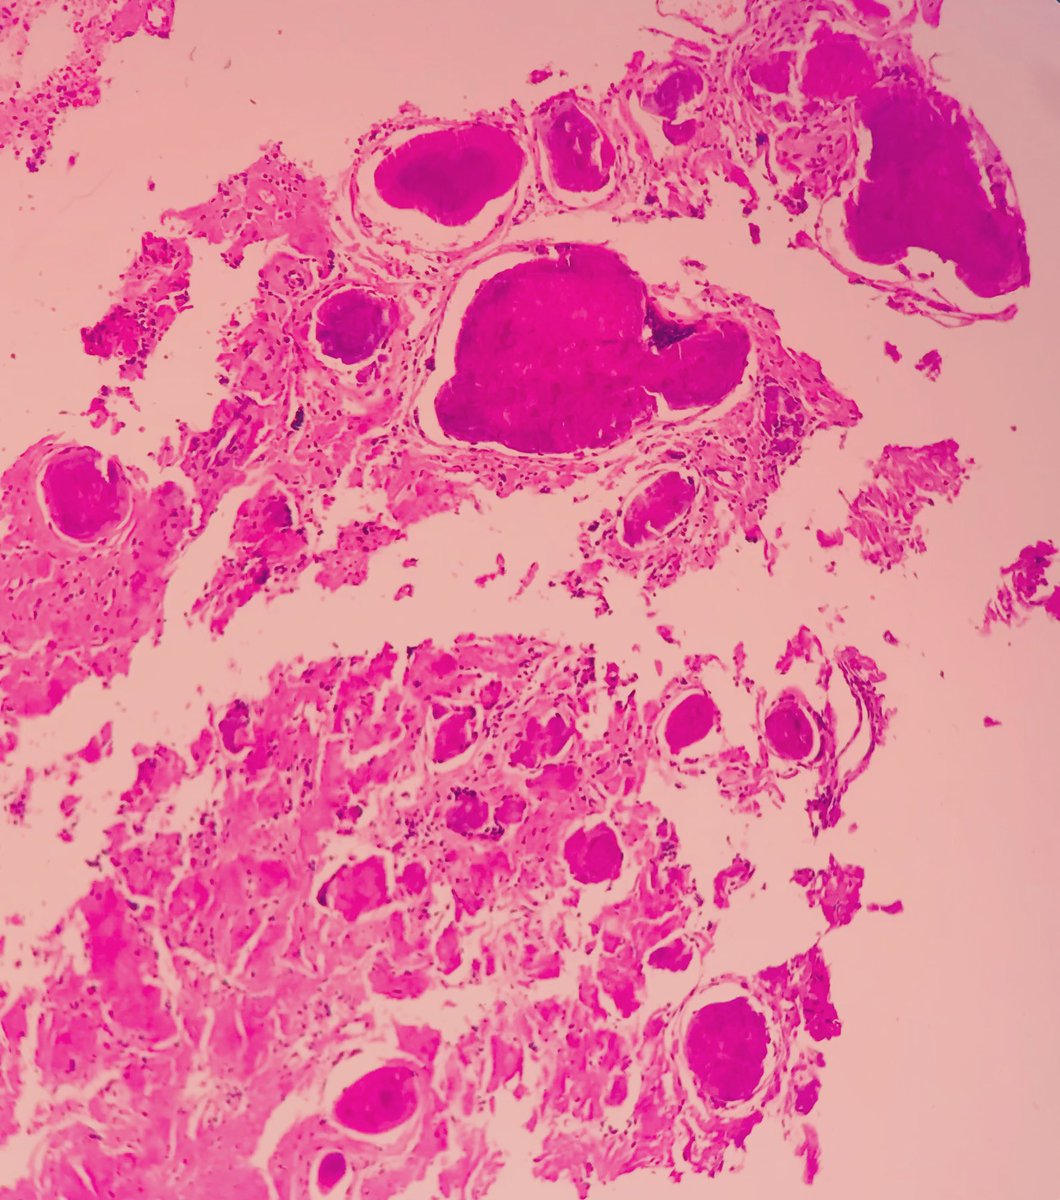

Amyloid deposition in true vocal cord in a young woman which is presented with dysphonia #Amyloidosis #PathTUMS #pathology

Amyloid deposition in true vocal cord in a young woman which is presented with dysphonia

#Amyloidosis

#PathTUMS

#pathology